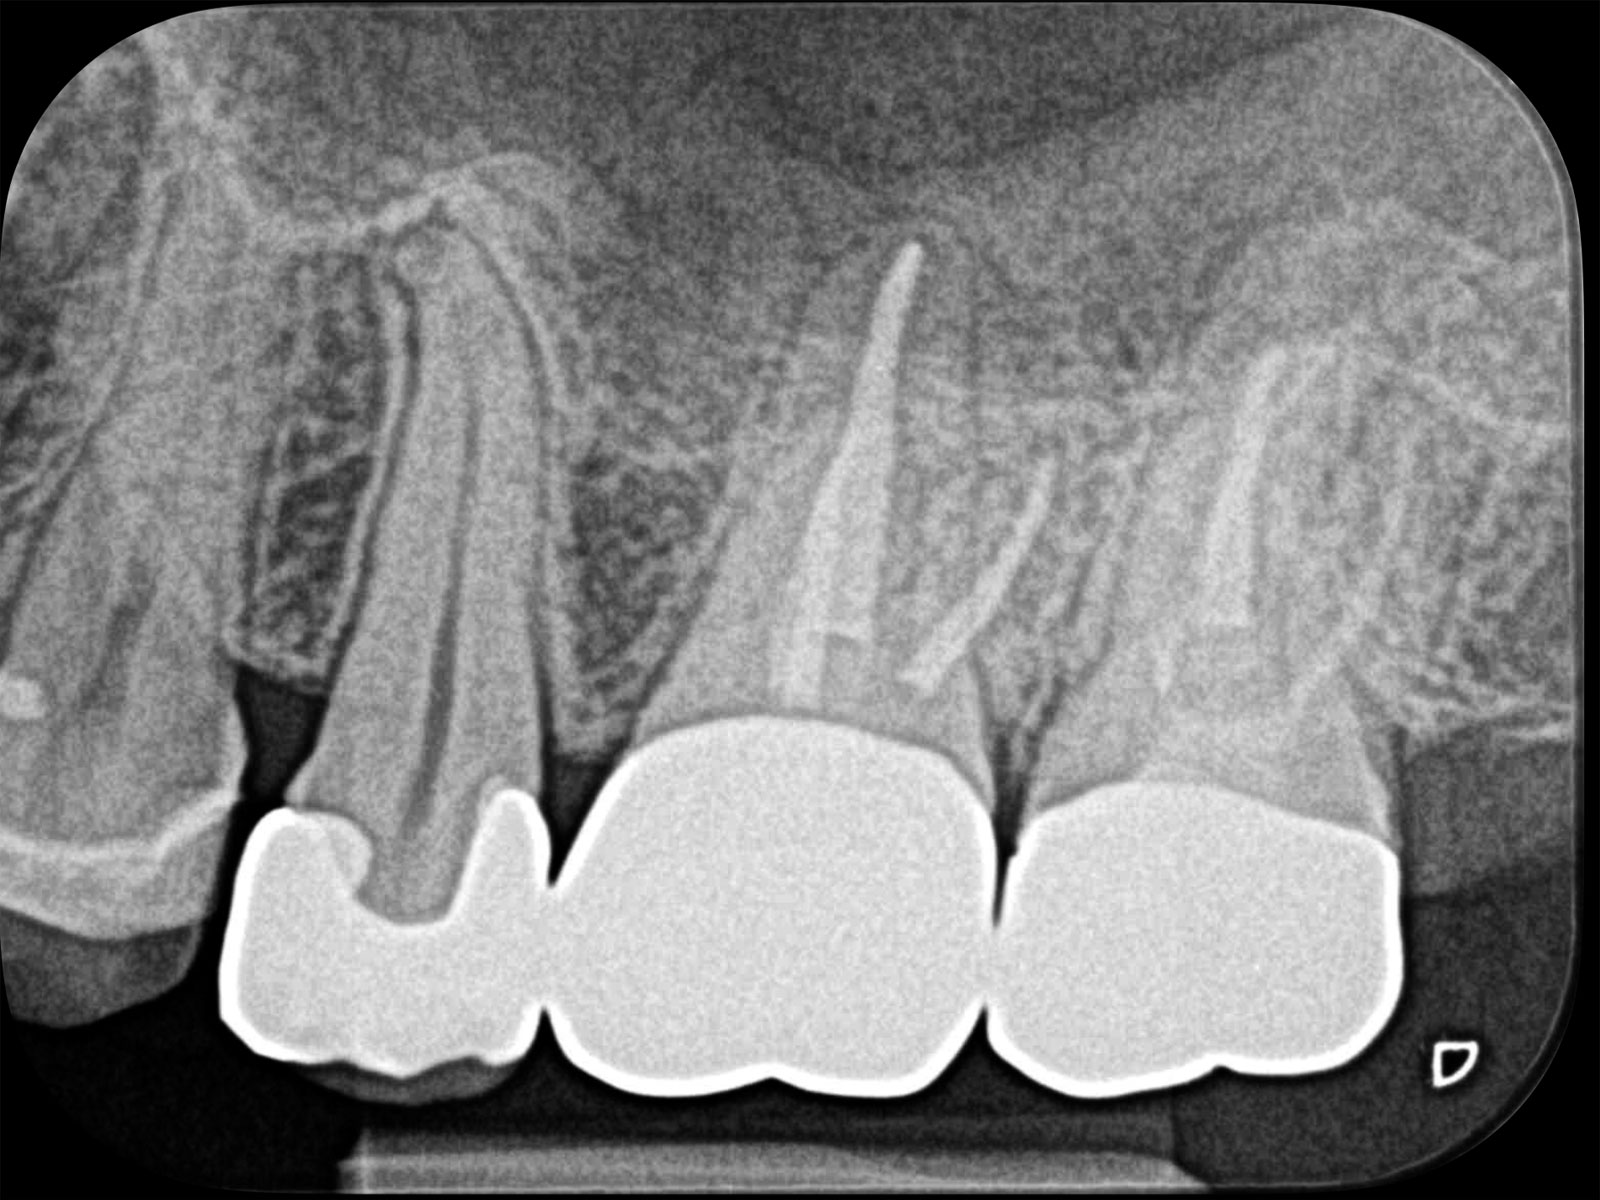

主訴: 右下がしみて痛い。

右下7根の根幹治療と親知らずの抜歯